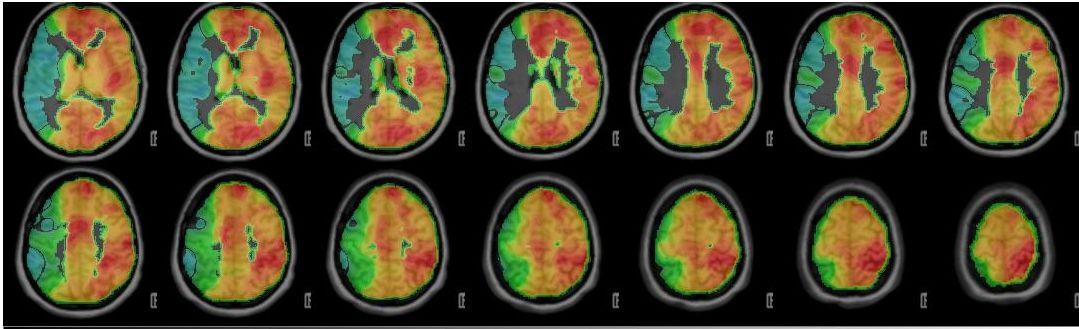

In der konventionellen Angiographie und im konventionellen MRT können selektiv die Gefäße, der Blutfluss, und das Gewebe gut dargestellt werden. Diese Untersuchungen erbringen jedoch keine Aussage über den absoluten Blutfluss im Gehirn. Adaptierte Untersuchungen des MRTs, sowie auch des CTs zur Messung der Hirndurchblutung (Perfusion) haben sich in der Vergangenheit bei Moyamoya Betroffenen auf Grund der Kollateralen als zu wenig sensitiv gezeigt, um die Durchblutung zuverlässig darzustellen.

Durch die Erforschung und Weiterentwicklung des funktionellen MRTs haben wir eine Untersuchung etabliert, welche die Reaktivität der Hirngefäße (und somit indirekt die cerebrale Durchblutungsreserve) darstellen kann. Beim sogenannten "breathhold", also Atemanhalte-fMRT müssen die Patientinnen und Patienten in mehreren Zyklen für jeweils wenige Sekunden die Luft anhalten. Dadurch erhöht sich die CO2-Konzentration im Blut und die Hirngefäße stellen sich weiter. Diese Veränderung des Blutflusses kann dann indirekt gemessen werden. Da es sich hierbei um eine sehr neue Methode handelt, ist zu erwähnen, dass medizinische Entscheidungen primär ausschließlich in Zusammenschau aller Befunde und bei jeglicher Unschlüssigkeit mit dem ergänzenden PET/CT getroffen werden. Das fMRT hat sich jedoch als exzellentes Screening-Tool und für die langfristigen Nachkontrollen erwiesen.

Wissenschaftliches Diagramm

Die Kurven zeigen die Veränderung der Vasoreaktivität bei einem Moyamoya-Patienten mit betroffener rechter Seite (hellgrüne Linie). Die linke Seite (dunkelgrüne Linie) und die Referenz (Kleinhirn-Cerebellum) zeigen einen adäquaten Anstieg der Kurven.